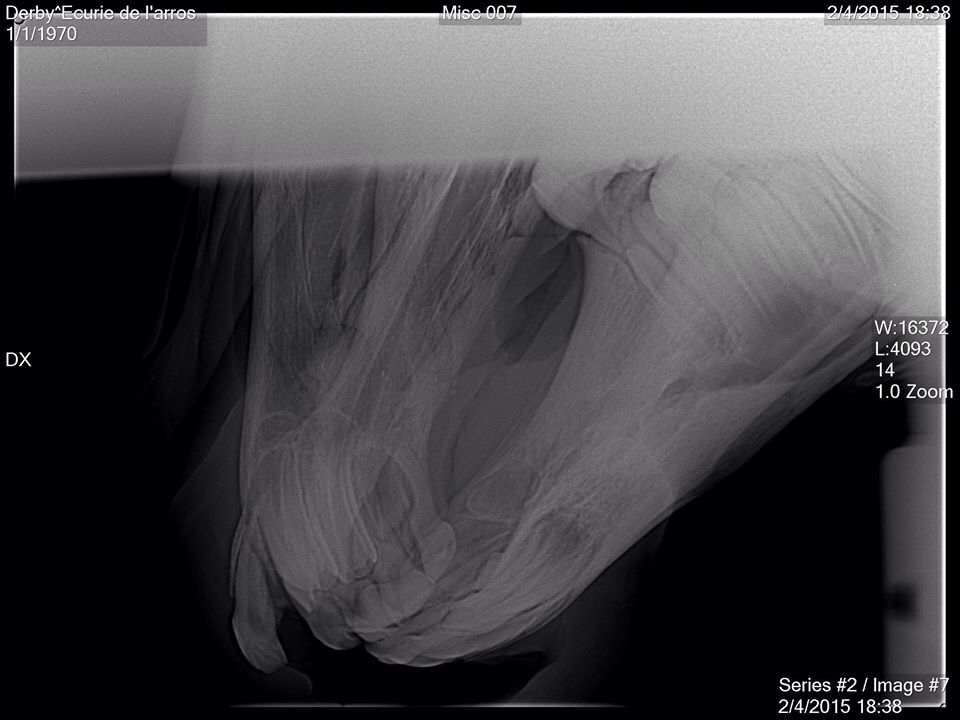

| Dire merci | Tout d abord desolee de ne pas vous avoir donné des nouvelles plus tôt . Le loulou va parfaitement bien, la dent etait bien fracturée, un cerclage a été réalise par l ecole veto de Nantes. Il est resté en place 6 semaines avant d être enlevé. Aujourdhui il est de nouveau au pré avec ses copains et tout va pour le mieux pour lui. Voici quelques photos: ![]() [/url] |

Par playboy78 : le 22/04/15 à 14:03:05

| Dire merci | ![]() [/url] ![]() [/url] ![]() [/url] ![]() [/url] ![]() [/url] |

| Dire merci | Et une fois le cerclage réalisé, l intervention a duré 2 bonnes heures, le chirurgien a beaucoup gratté la gencive pour pouvoir remettre la dent à sa place. Le travail realisé est vraiment superbe, on ne se rend aujourdhui quasiment plus compte de ce qui lui est arrivé.![]() [/url] |